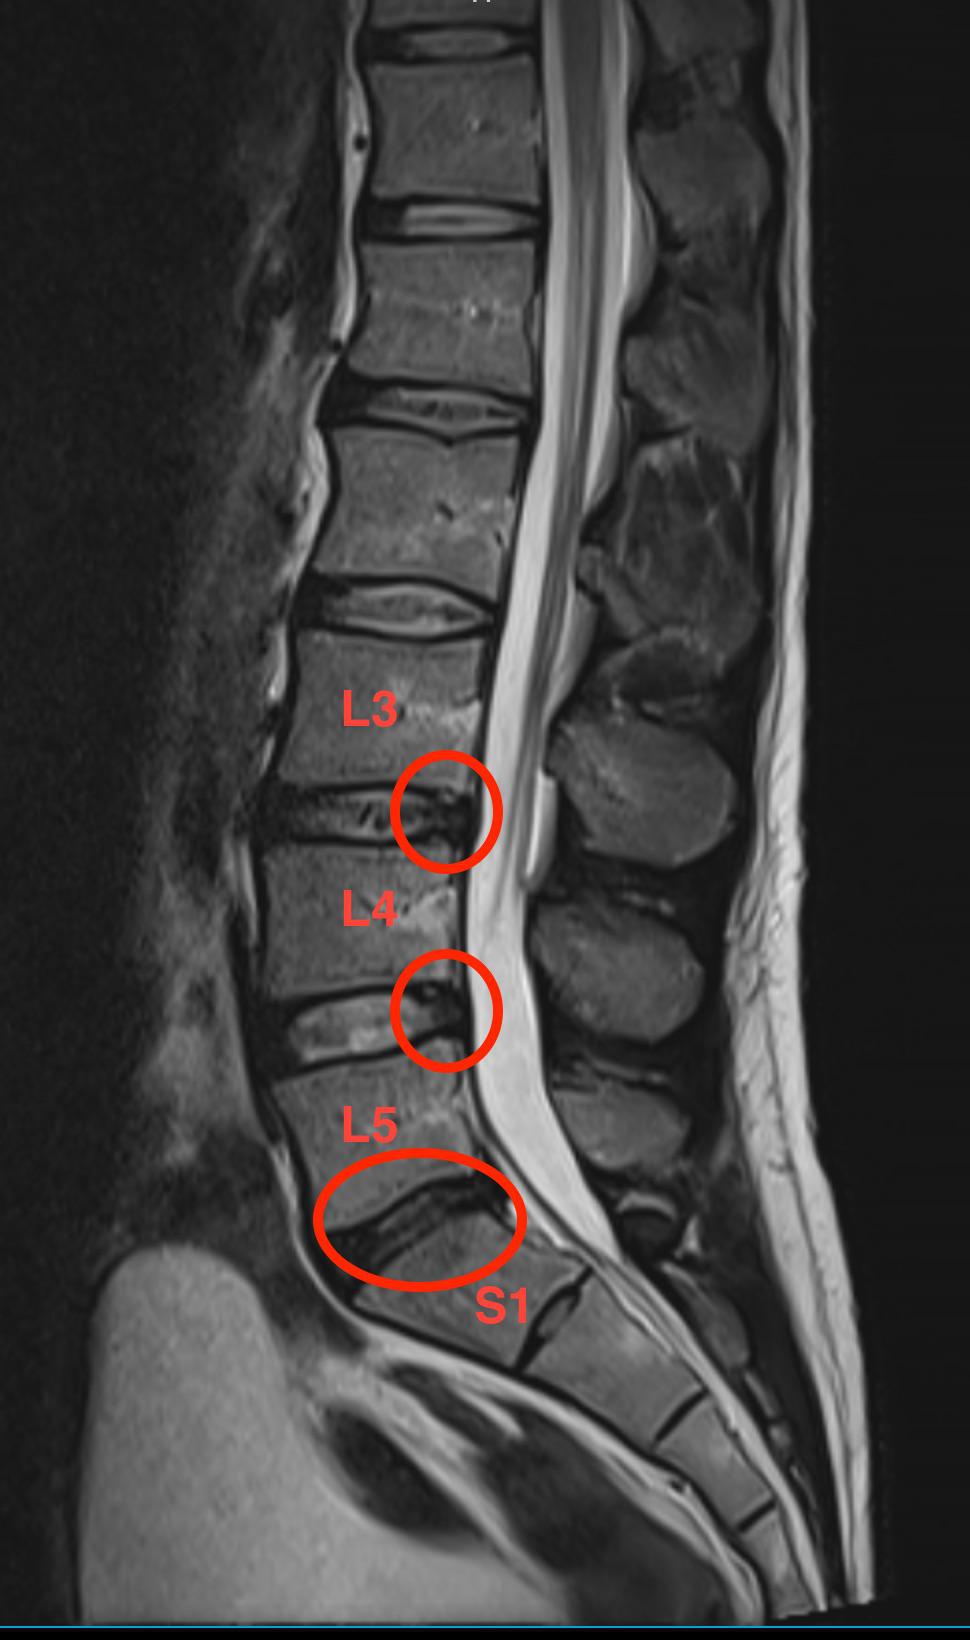

T2weighted sagittal MRI image, disc herniation in L4L5 and L5S1 Slipped Disc Between L4 And L5 Thankfully, early diagnosis and proper treatment can lead to relief and an improved quality of life. It can be painful, but there are treatments that can help. A change in disc height. The disc often puts pressure on a nerve root which causes pain down one leg. Spondylolisthesis is where one of the bones in your spine, called a vertebra,. Slipped Disc Between L4 And L5.

Sagittal MRI demonstrates L4L5 herniated nucleus pulposus and L5S1 Slipped Disc Between L4 And L5 Difficulty in lifting a foot, a condition known as “foot drop”. Additionally, in rare cases, a bulging or ruptured disc in the lower back can cause a. A slipped disc often causes sudden severe lower back pain. A change in disc height. Spondylolisthesis is where one of the bones in your spine, called a vertebra, slips forward. Thankfully, early diagnosis. Slipped Disc Between L4 And L5.